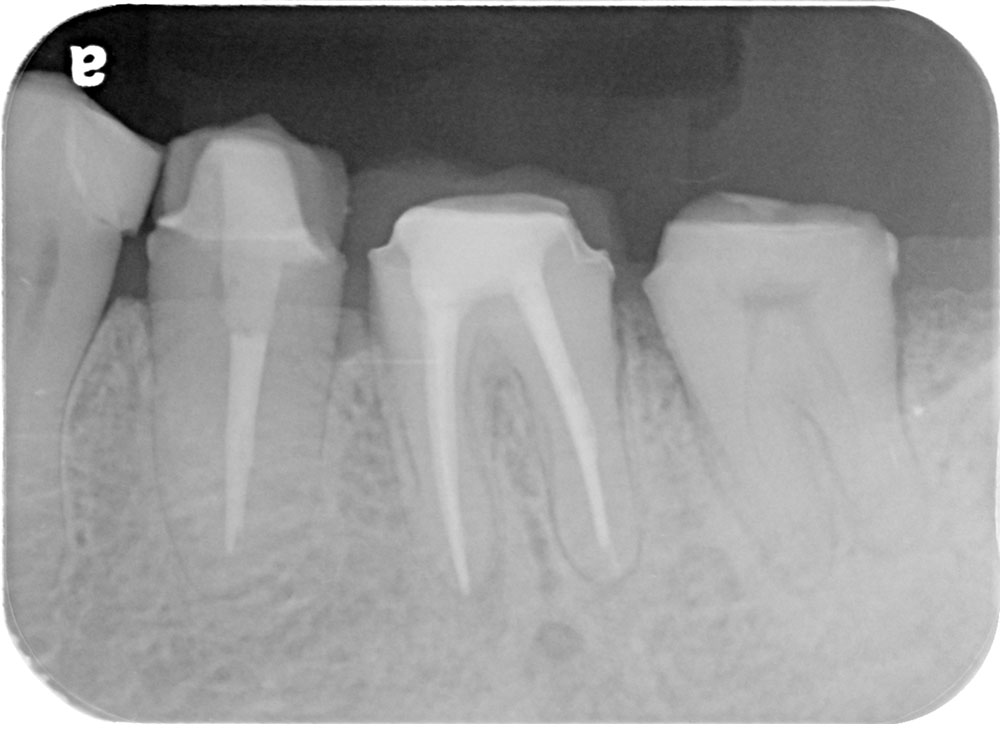

術前

治療内容

根管治療

治療期間

2ヶ月

治療費

保険適応内

治療のリスク

治療中または治療後に、一時的な痛みや腫れが生じることがある